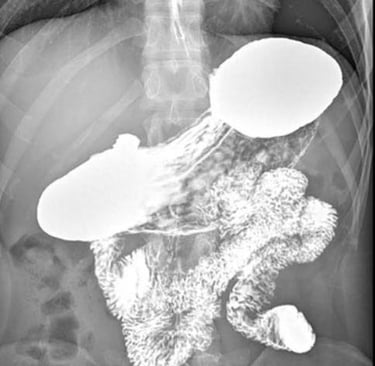

Il paziente ingerisce un liquido contenente solfato di bario (radiopaco), che riveste le pareti esofagee e permette di visualizzarle ai raggi X.

Si eseguono radiografie statiche e fluoroscopia dinamica per osservare il passaggio del contrasto attraverso l’esofago fino allo stomaco.

📌 Reflusso gastroesofageo (GERD) → Visualizzazione del contrasto che risale dallo stomaco nell’esofago.

📌 Acalasia → Dilatazione dell’esofago con segno a becco di uccello.

📌 Stenosi esofagea → Restringimenti o aree di ostruzione.

📌 Diverticoli esofagei → Pouch o estroflessioni della parete esofagea.

📌 Ernia iatale → Dislocazione dello stomaco attraverso il diaframma.

📌 Spasmo esofageo diffuso → Contrazioni irregolari e non coordinate dell’esofago.